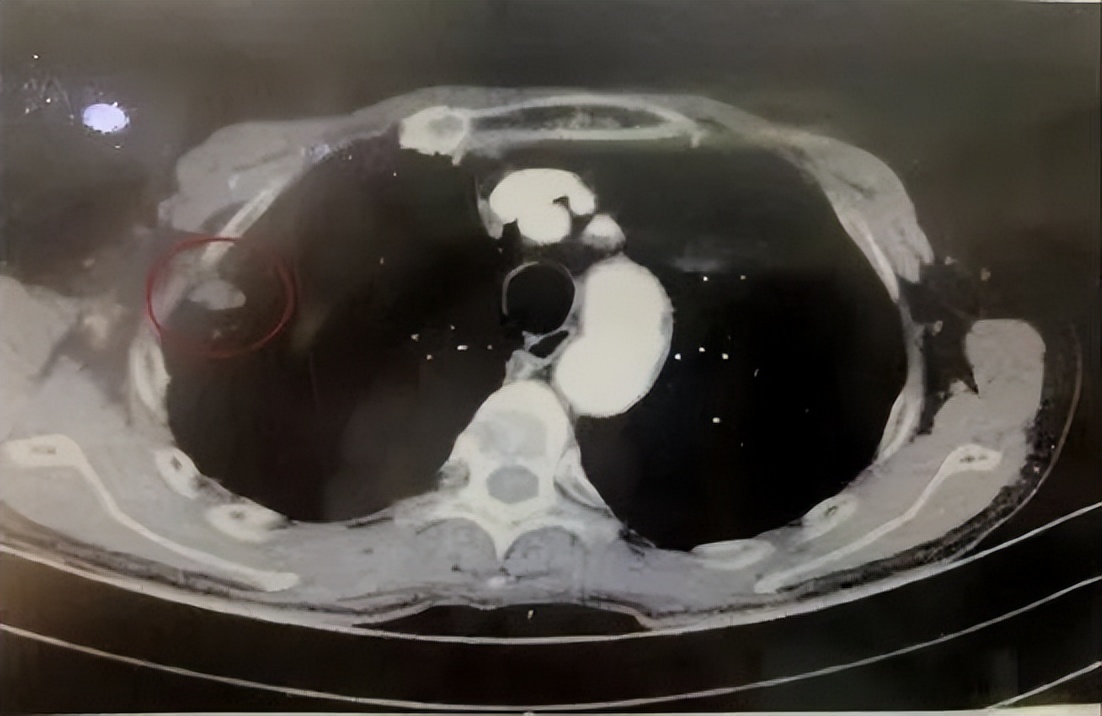

患者右上肺小肺癌,本身年龄大、身体情况差,拒绝手术治疗。

CT引导下射频针插入右上肺癌,高温消融灭活肿瘤。